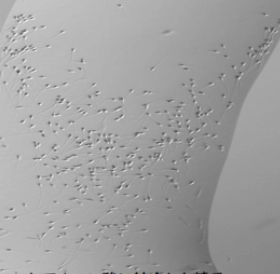

- 回収した卵胞液から顕微鏡で卵子を探します。

このような場合に行う治療法が「顕微授精」です。顕微授精はこれまで数通りの方法が開発されましたが、現在は微細な極細のガラス管に精子を一個だけ吸引して、直径0.1mmの卵の卵細胞質内に直接注入する方法(ICSI:イクシー:卵細胞質内精子注入法)が主流です。

顕微授精は、1992年、ベルギーで初めてヒトで成功して以来、成功例は数百万例を越えています。この方法だと、精子の動きが悪くても、遺伝子を司るDNAさえしっかりしていれば、卵1個に精子1個だけで受精できるので、非常に効率的です。

IMSI(高倍率による精子選別)

顕微授精を行う際には、卵子あたり1個の精子を選別する必要があります。培養室では、形態や運動能を指標としてより良い精子を顕微授精に供するようにしています。

IMSIは、通常の顕微授精を行う際の倍率よりもさらに高倍率で精子頭部を観察する方法です。これによって、通常は確認できない形態的異常(空胞など)を持つ精子を除くことができます。精子の奇形率が高く、通常のICSIでは受精できなかった場合や受精卵の発生があまり良くなかった時などに使用していきます。

600倍観察:通常の顕微授精での倍率

1000倍観察:IMSIでの倍率